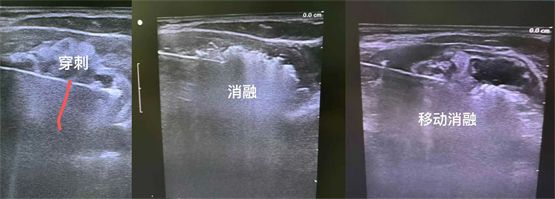

整个治疗在超声的引导下进行。B超扫描定位,首先以左侧甲状腺肿物为靶区,B超引导下,用细针行穿刺活检,送术中快速病理检查,结果提示为未见癌细胞。因肿物巨大,术中还在甲状腺与气管间隙、与左侧颈总动脉间隙、与食管间隙,注射生理盐水进行水隔离处理,增大治疗组织与周围组织的间隙,保护周边气管、食管、颈部大血管、喉返神经、喉上神经等重要组织结构。

随后,以30W的功率开始微波消融。按由下至上,由内至处,由深至浅的顺序动态调整数微波刀位置,直至消融范围覆盖靶区,拔除微波刀。就这样,梅丽的甲状腺结节被逐步“瓦解”。

微波消融巨大甲状腺肿物